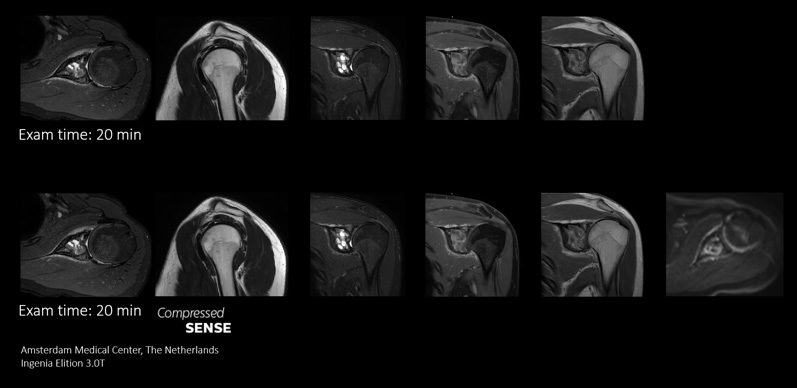

Replace Sequences scan

With Compressed SENSE you can replace your single orientation 2D FLAIR scan with a multi-orientation 3D volumetric FLAIR scan in only 3 and a half minutes scan time.

I do a lot of brain imaging, and we used to do the FLAIR sequence using a 5 mm thick slice. Now with Compressed SENSE we are able to take a 3D volumetric scan for about 6 minutes down to maybe 3 and a half minutes.”

Dr. Mark Oswood, MD, PhD, Neuroradiologist, Hennepin Healthcare, Minneapolis, USA